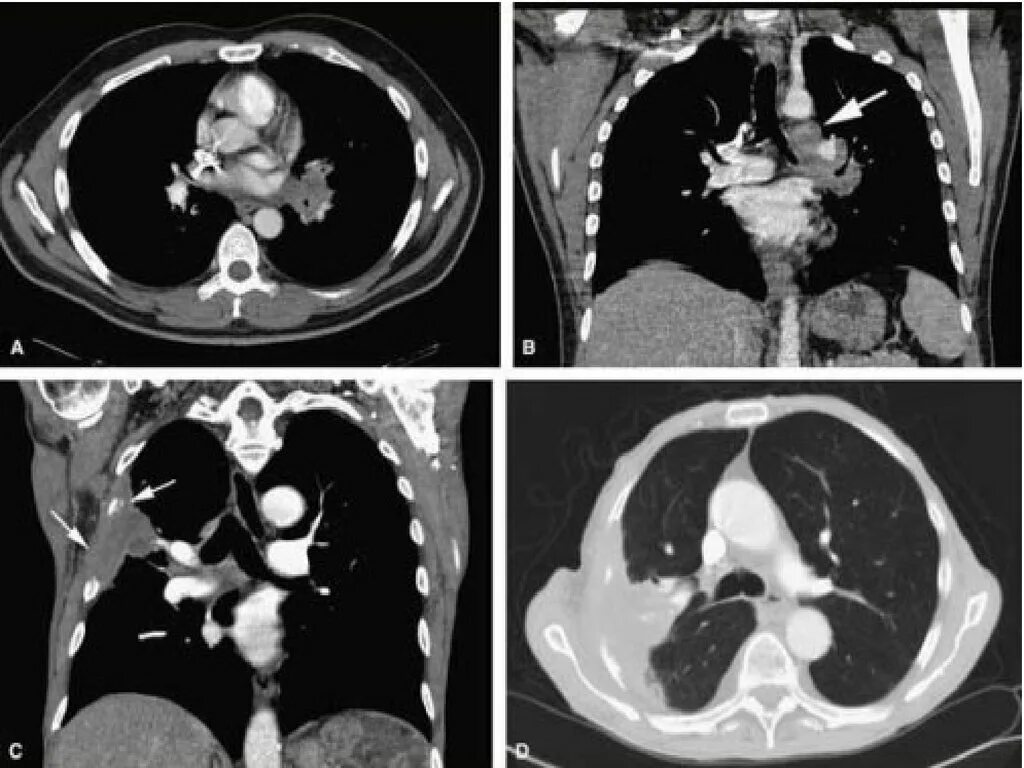

Как на кт выглядит рак